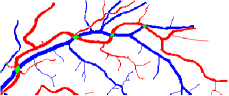

In this paper, we propose a coherence-penalized minimal path model, where the associated minimal paths favour to pass by a vessel that is located in the flatten region of an external feature map. We observe that along a piece of retinal vessel, the values of gray levels vary slowly. More specifically, retinal arteries have lower contrast of gray levels than veins due to the blood materials and imaging modality. In other words, in some extent the arteries and veins are distinguishable in terms of vesselness values. Such an observation can be used to solve the short branches problem that the minimal paths associated to a metric may pass through segments belonging to different vessels as shown in Figs. 1b and 1c. Fig. 1d shows the result from the proposed method, which can avoid such problem. Fig. 1a gives the artery-vein (AV) groundtruth. In this paper, we denote by blue and green dots the source and end points respectively.

Compare to existing minimal path models. The Riemannian metrics used in [1, 4, 5] are based on the local pointwise information. The curvature-penalized metric [7, 6] and the proposed coherence-penalized metric are able to consider more constraints, i.e., the rigidity for [7, 6] and feature coherence for our metric. These constraints are beneficial to the respective geodesics to reduce the risk of short branches combination problem. Compared to the curvature-penalized metric, our method can be more flexible since the feature map can be produced dependently on the task. In retinal imaging, veins and arteries are distinguishable in terms of gray levels or vesselness values, satisfying the formulation of the proposed model. Especially for vessels with strong tortuosity, the curvature-penalized metric, which favours a smooth curve, fails to catch the expected vessels as shown in the left column of Fig. 2. From the right column of Fig. 2, one can see that our model can obtain a good result.